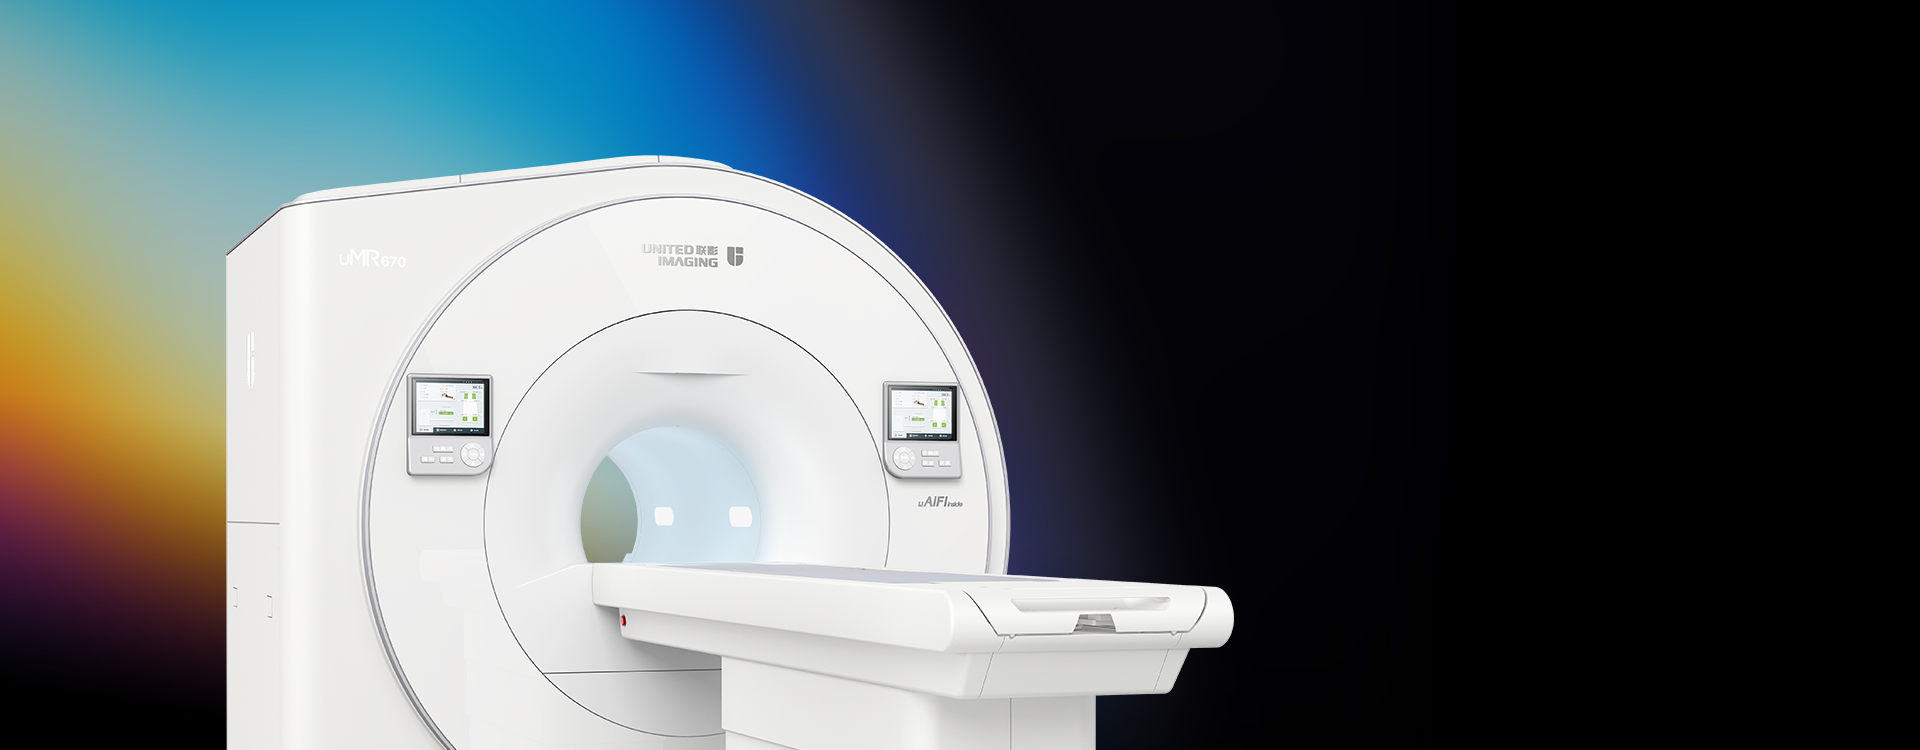

「准3.0T」大孔径1.5T磁共振

「准3.0T」大孔径1.5T磁共振

uMR 670全面搭载uAIFI Technology磁共振“类脑”技术平台,开创性实现高性能系统与深度学习图像重建技术的完美融合,引领大孔径1.5T全面进入“准3.0T”成像新时代。

搭载uAIFI Technology技术平台,凝聚多项全球首创核心技术,全链条革新磁共振硬件、软件设计,实现系统性能、扫描智能化、成像速度与信噪比的大幅提升,同时赋予患者更舒适的检查体验,开启磁共振“类脑”时代。